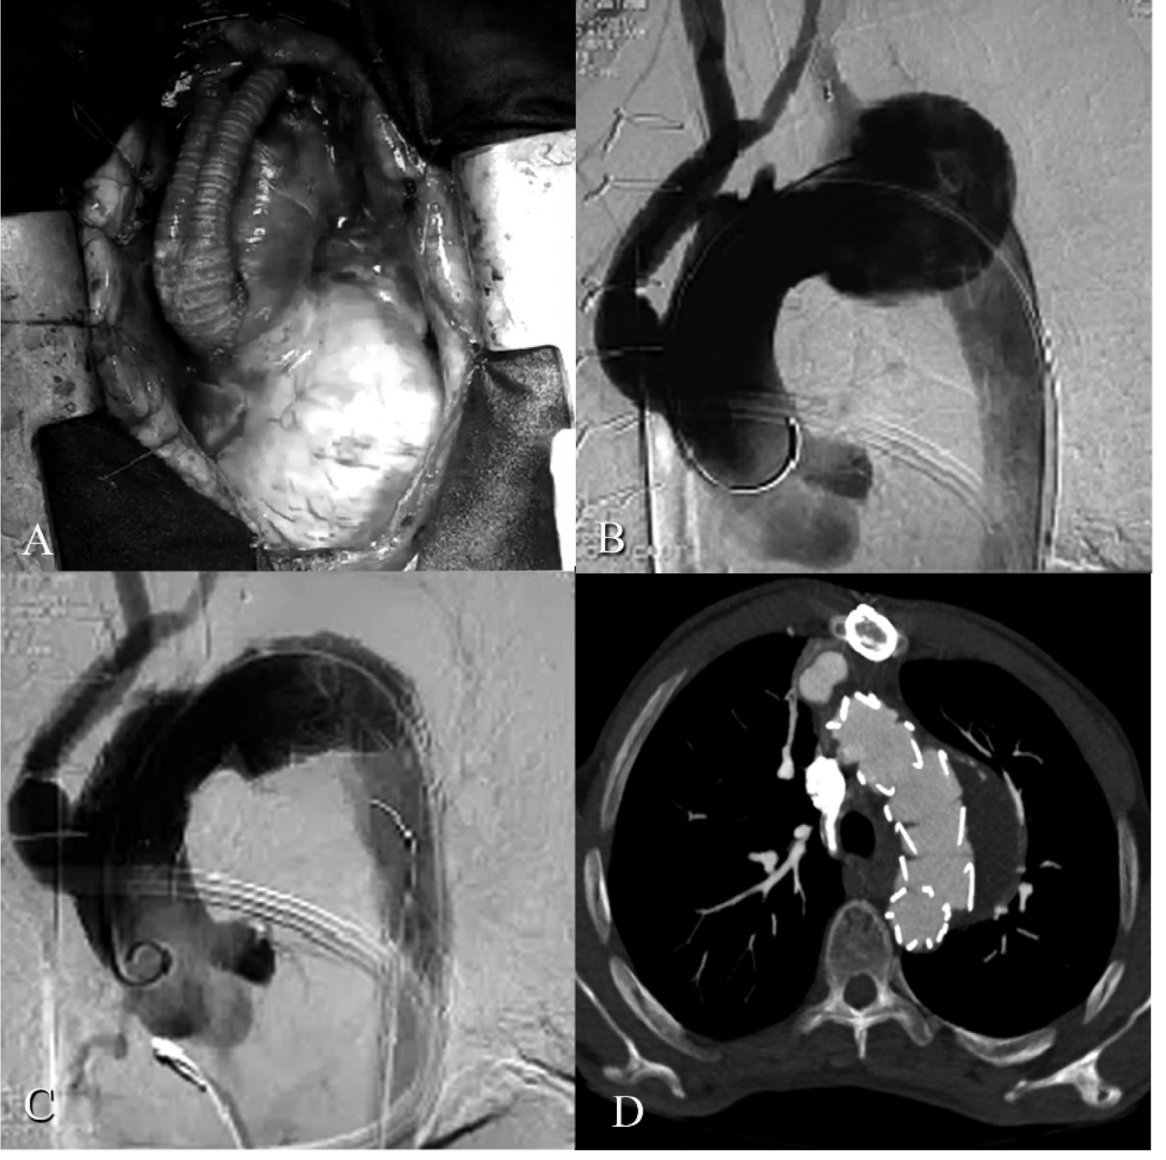

该患者没有神经系统并发症的证据,并且在24小时内出院,生命体征稳定,无症状。混合手术后5天内进行CT血管造影扫描(图2)。

图2: A)分支无名和左颈动脉后升主动脉的术中视图;B)主动脉根部注射后的造影图像; C)支架部署后相同的血管造影图像;D)手术后5天进行CT血管造影。动脉瘤囊血栓形成